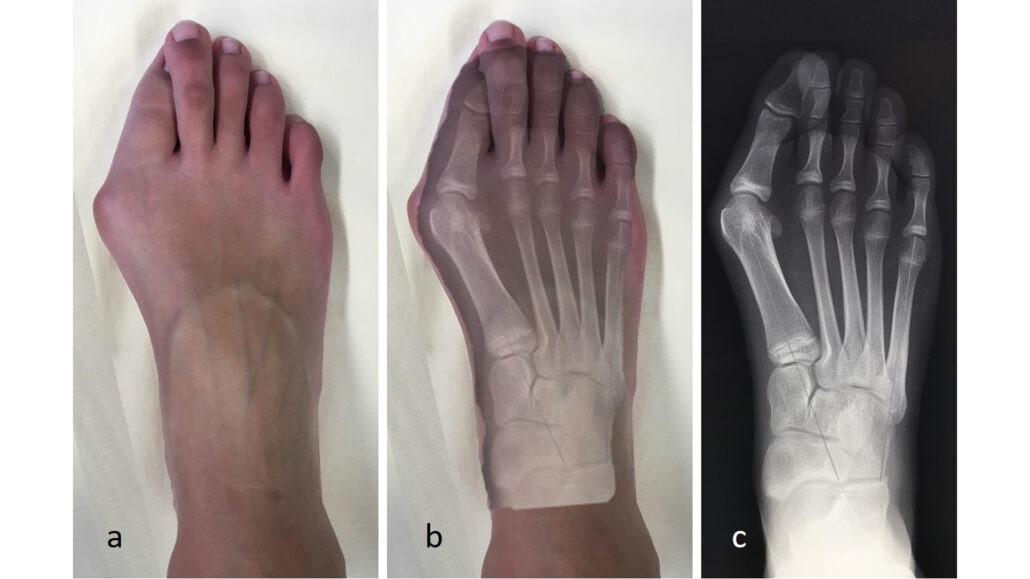

Hallux Valgus

L’Hallux Valgus, souvent appelé « oignon », est une déviation du gros orteil provoquant une bosse douloureuse, favorisée par l’hérédité et le port de chaussures étroites. Lorsque le chaussage devient difficile malgré les traitements médicaux (semelles, orthèses), la chirurgie permet de corriger durablement l’axe osseux. L’intervention est peu douloureuse et autorise une marche immédiate avec une chaussure spécifique, bien que le pied nécessite plusieurs mois pour dégonfler totalement.